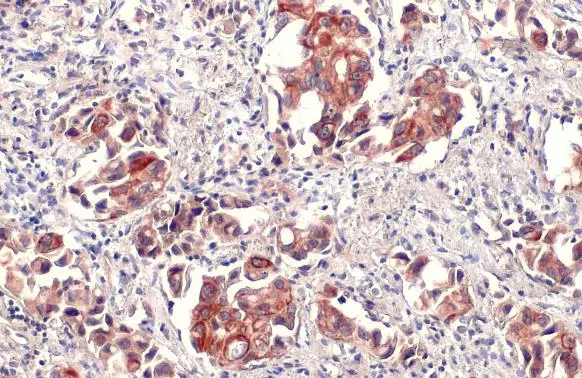

Anti-IL6 antibody used in IHC (Paraffin sections) (IHC-P). GTX110527

GTX110527 IHC-P Image

IL6 antibody detects IL6 protein at cell membrane and cytoplasm by immunohistochemical analysis.

Sample: Paraffin-embedded human lung cancer.

IL6 stained by IL6 antibody (GTX110527) diluted at 1:500.

Antigen Retrieval: Citrate buffer, pH 6.0, 15 min